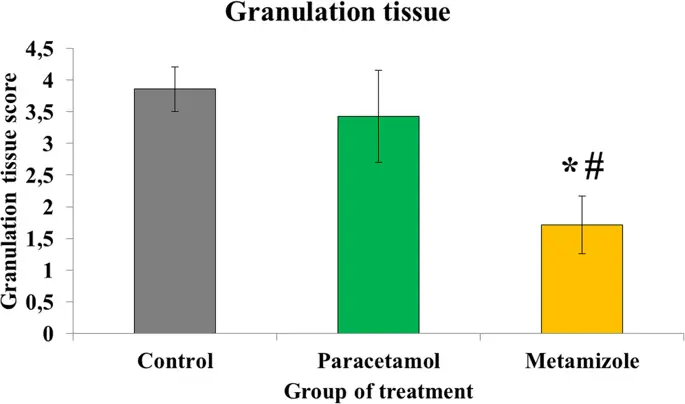

Образование грануляционной ткани на толстом кишечнике анастомоза было более подавлено в группе метамизола (1, 71 ± 0, 5), чем в парацетамоле (3, 43 ± 0, 8) и контрольной группе (3, 86 ± 0, 4) (р <0, 05). Кроме того, образование грануляционной ткани было сопоставимо между парацетамолом и контрольной группой (р> 0, 05) ( рис. 3).

Оценка грануляционной ткани на стороне анастомоза толстой кишки крысы (*, метамизол против контроля, р <0, 05; #, метамизол против парацетамола, р <0, 05). Низкие значения, указывающие на худшую грануляцию ткани

Изображение в полном размере